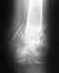

После родов (2 года назад) у меня вертикальная нестабильность тазового кольца. Очень болит правое заднее сочленение.

При этом щель лонного сочленения всего 5 мм. Это только операция поможет, или как-то еще можно вылечить?Еще где можно уточнить, о сроках реабилитации после операции (если все же придется делать)